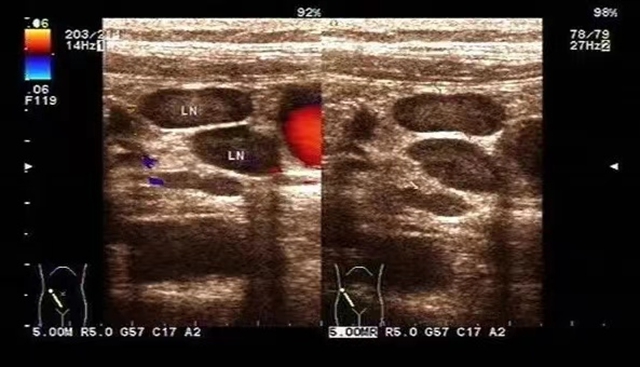

超声检查可清晰显示肠系膜淋巴结多发肿大。淋巴结肿大大小不等,多位于脐周或右下腹,有些患儿可见呈多个簇状、堆状分布;其外形光滑、完整,皮髓质分界清(部分皮质增厚),呈低回声,其内回声均匀,一般无融合或钙化。部分淋巴结内血流信号增加。